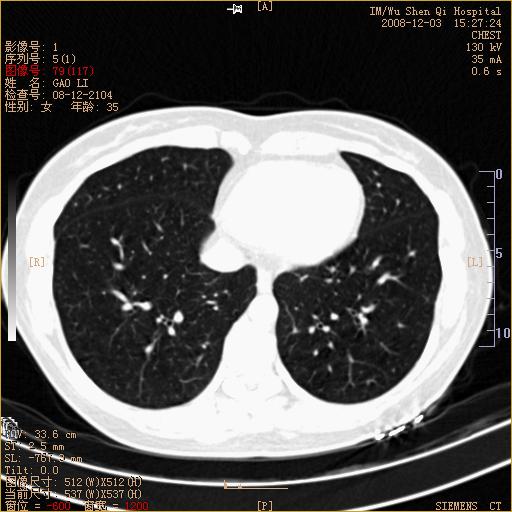

标题: CT16895:女,35岁,反复咳嗽数月,只传部分图像,是否考虑 [打印本页]

标题: CT16895:女,35岁,反复咳嗽数月,只传部分图像,是否考虑

左下肺支扩

典型“印戒征”。

印戒征,支持支扩.

左下肺扩支

印戒征,支扩